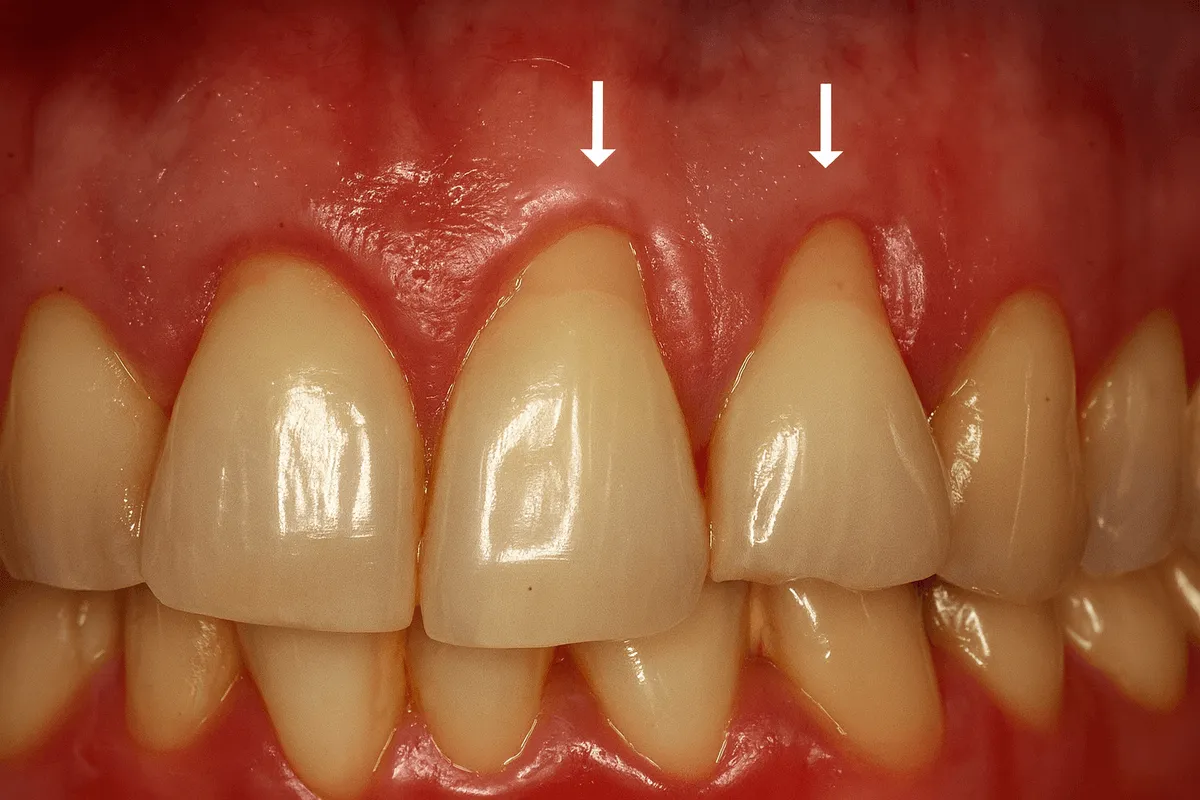

Gingivita este inflamația gingiei apărută, cel mai des, din cauza acumulării plăcii bacteriene pe dinți, în special la linia gingiei. Placa are bacterii care eliberează substanțe iritante, iar gingia răspunde prin roșeață, umflare și sângerare la periaj sau ață dentară.

Cele mai frecvente semne sunt sângerarea la periaj sau folosirea aței dentare, gingii roșii și umflate, sensibilitate locală și respirație neplăcută persistentă.